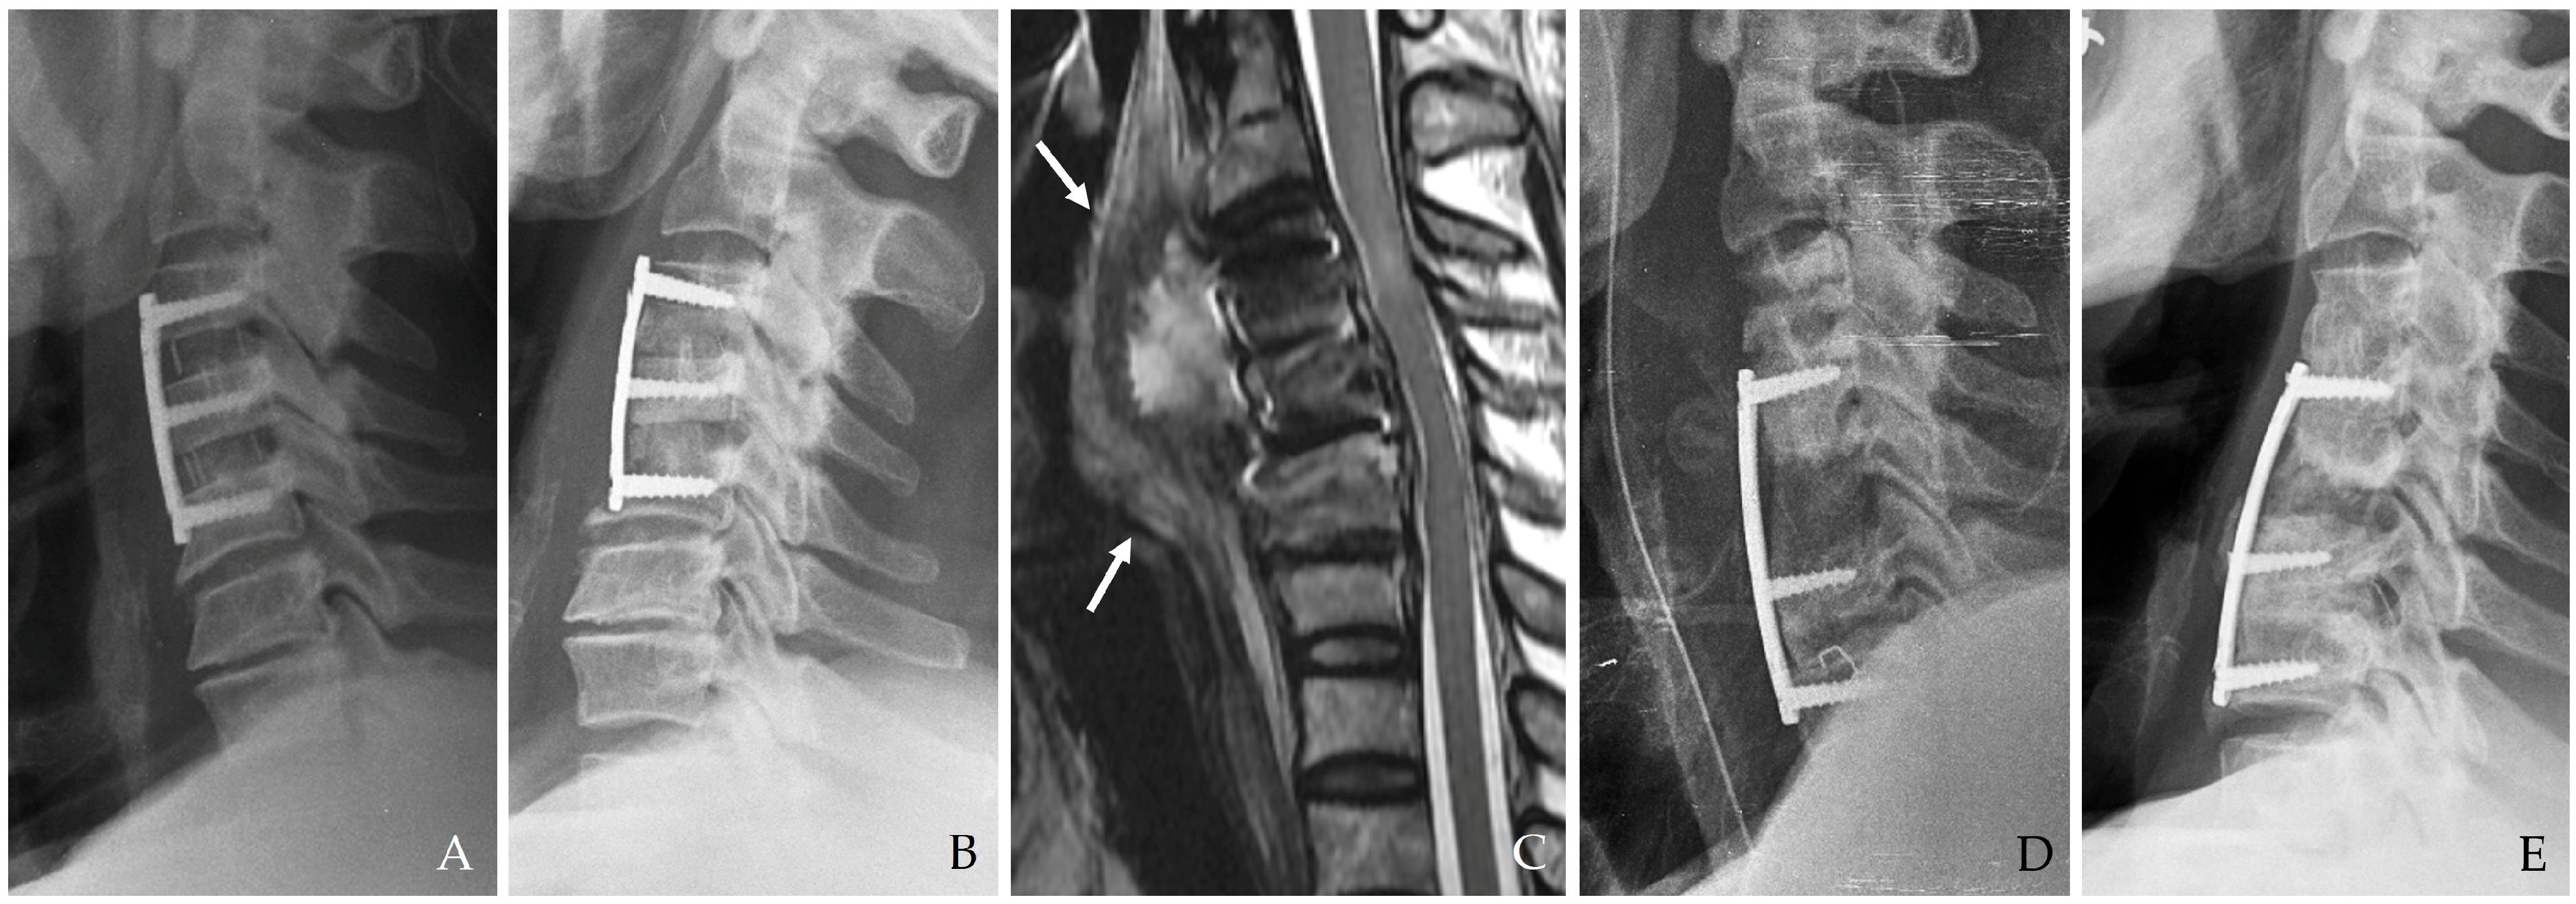

Figure 1. The patient underwent C3-4-5 anterior cervical discectomy and fusion (A). At postoperative 2 months, postoperative infection occurred with retropharyngeal abscess (white arrows) and epidural abscess (B,C). Therefore, the patient underwent evacuation of retropharyngeal and epidural abscesses, irrigation/debridement, and revisional C5-6-7 corpectomy and fusion (D) and achieved a cure for the infection (E).

Anterior cervical spine surgery is a critical intervention for a variety of conditions ranging from degenerative disc diseases and traumatic injuries to neoplastic disorders. Although significant improvements have been achieved in surgical techniques, perioperative infection control, and postoperative care, the risk of postoperative infection remains a serious concern [1,2,3]. While the overall incidence of infection in cervical spine surgery is relatively low compared to lumbar procedures due to superior local vascularity and less extensive soft tissue dissection, the anatomical proximity of the cervical spine to vital neurovascular structures and the esophagus creates a high-risk environment for severe complications (Figure 1) [1,2,4,5].